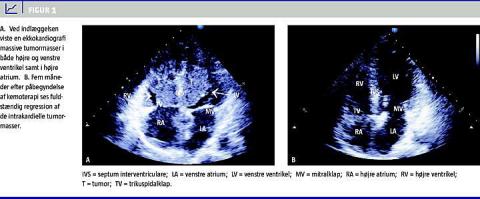

En tidligere hjerterask 44-årig somalisk kvinde blev indlagt med utilsigtet vægttab og ukarakteriske brystsmerter og dyspnø af tre måneders varighed. Paraklinisk fandt man ved indlæggelsen let forhøjet laktatdehydrogenasekoncentration på 350 U/l, men et normalt antal leukocytter, C-reaktivt protein og koronarmarkører i blodet. Objektivt fandt man palpable lymfeknuder på collum og i begge aksiller. Stetoskopisk fandt man systolisk mislyd over prækordiet, og et elektrokardiogram viste inverterede T-takker i V1-V4. En ekkokardiografi viste massive processer i både højre og venstre ventrikel. Tumormasserne var adhærente til septum og syntes at vokse infiltrativt i myokardiet (Figur 1 A). Tumormasserne målte 5 × 2 cm i hver ventrikel. Derudover var der mindre tumormasser i højre atrium. Venstre ventrikels systoliske funktion var bevaret. De mobile tumormasser medførte intermitterende obstruktion af udløbsdelen af venstre ventrikel med intermitterende peak-gradienter ved Dopplerflowmåling på op til 60 mmHg. Mitralklappen og trikuspidalklappen var fri af tumoren. Der var intet perikardieekssudat. Vena cava inferior målte 1,7 cm i diameter, men var uden respiratorisk variation. En ultralydskanning af halsen viste multiple forstørrede lymfeknuder bilateralt. Man foretog derefter transvenøs myokardiebiopsi (MYBI) samt glandeleksstirpation fra halsen.

Fem måneder senere blev patienten indlagt med tiltagende svimmelhed og dobbeltsyn. Hun var på dette tidspunkt fuldt supprimeret i hiv-RNA, og CD4-tallet var 50 celler/mm 3 . En kontrolekkokardiografi viste fuldstændig regression af de intrakardielle tumormasser, og venstre ventrikels systoliske funktion var fortsat bevaret (Figur 1B). Ved lumbalpunktur og flowcytometri af spinalvæske kunne der ikke påvises lymfomceller. En magnetisk resonans (MR)-skanning af cerebrum viste opladning omkring ventriklerne, hvilket er suspekt for cerebrale metastaser. Dette blev bekræftet ved en positronemissions-CT. Patienten blev behandlet med vincristin, methotrexat, prednisolon og procarbacin suppleret med intratekal kemoterapi. På trods af dette aggressive regime var der progression af tumoren. Patienten gik efter kort tid ad mortem.